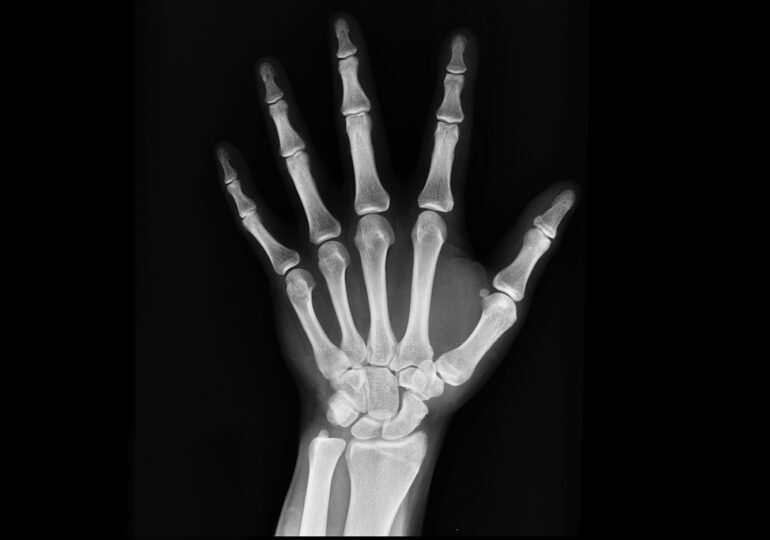

Noua cercetare e practic o analiză a nu mai puțin de 60 de studii efectuate pe culturi celulare și animale, care explorau efectele microplasticelor. Pe baza acestor date, analiza a arătat că particulele pot stimula formarea unor celule numite osteoclaste, responsabile de degradarea țesutului osos vechi pentru a-i face loc celui nou.

Însă, combinată cu alte efecte negative asupra sănătății celulare, în special reducerea numărului de globule albe și perturbarea microbiotei intestinale, această stimulare excesivă dezechilibrează ciclul natural al regenerării osoase, scrie Futurism.

Osteoclastele ajung astfel să distrugă mai mult țesut decât organismul poate să refacă, ceea ce duce la slăbirea oaselor, deformări și fracturi. Mai grav, potrivit cercetătorilor, poate chiar împiedica dezvoltarea normală a scheletului, se arată într-un raport publicat de jurnalul Osteoporosis International.